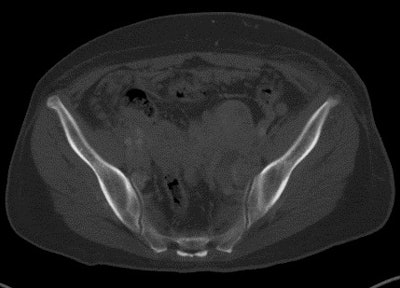

Most interestingly, given there were 197 malignant lesions in the spine, as seen on PET/CT, CT alone missed 153 malignant lesions (77%) in the spine. CT did not fare particularly well in the pelvis, missing 80 (71%) of the 113 malignant lesions in this area. (See chart.)